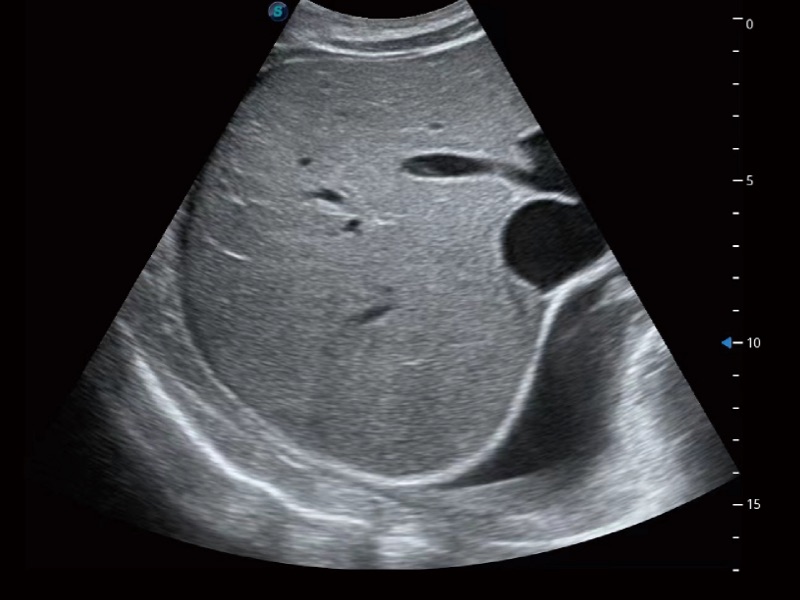

• 腹部应用

• 光影成像

临床图